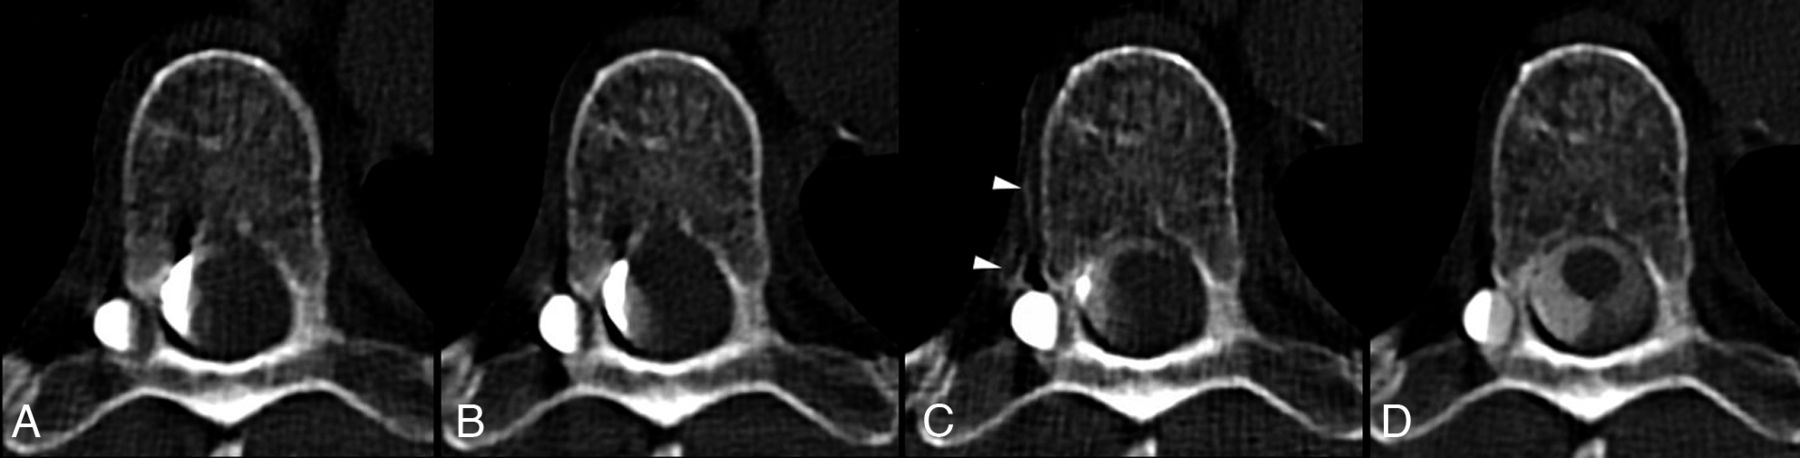

Axial images from a right lateral decubitus dynamic CT myelogram with bolus-tracking that were acquired at 30 seconds (A), 60 seconds (B), 2 minutes (C), and 4 minutes (D) after dense contrast was visualized on the bolus-tracking. A CSF-venous fistula is clearly identified on the image acquired at 2 minutes, with contrast visualized in a right T7 paraspinal vein (C, arrowheads). Note that the CVF only becomes more prominent after the adjacent diverticulum has nearly been completely filled with contrast.